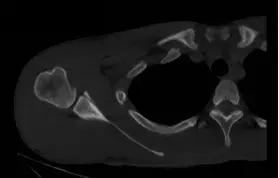

右肩关节CT影像

经再三考虑之后,他找到罗湖医院集团关节病与运动医学科卢启贵主任团队,卢主任对黄嘉俊进行了详细的问诊与查体,“右肩骨性Bankart损伤”诊断明确,且经正规保守治疗后无效果,因此卢主任建议他接受关节镜手术治疗。

经术前CT三维模型重建,科室讨论制定详细手术方案后,10月23日,卢启贵主任亲自为黄嘉俊施行了“关节镜下关节盂唇修复术”,手术非常成功。